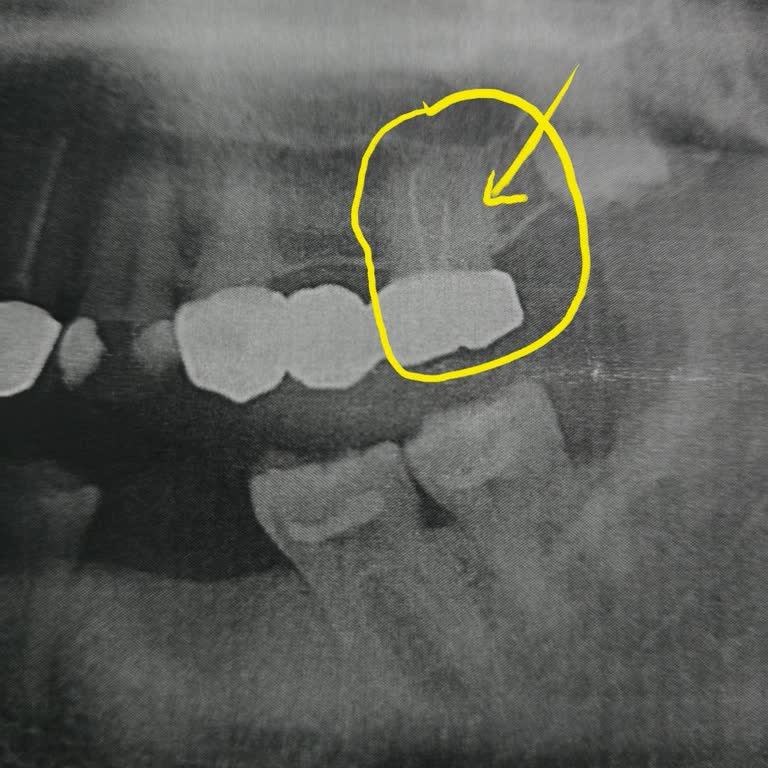

2023 yılında mesam Diş’te bir dişime kanal tedavisi yaptırdım. Tedaviden birkaç ay sonra aynı dişimde tekrar ağrılar başladı ve şikayetlerim giderek arttı. Ağrılarım üzerine tekrar mesam Diş’e gittiğimde, sorunun devam etmesine rağmen benden yeniden ücret talep edildiği için tedaviye devam etmedim....